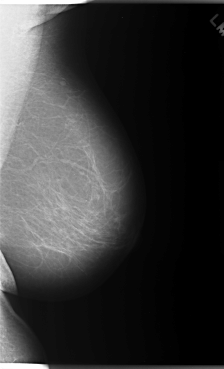

C_0086_1.RIGHT_MLO

RIGHT_MLO LINES 5904 PIXELS_PER_LINE 3600 BITS_PER_PIXEL 12 RESOLUTION 50 OVERLAY

FILE: C_0086_1.RIGHT_MLO.OVERLAY

TOTAL_ABNORMALITIES 1

ABNORMALITY 1

LESION_TYPE MASS SHAPE LOBULATED MARGINS MICROLOBULATED

ASSESSMENT 5

SUBTLETY 5

PATHOLOGY MALIGNANT

TOTAL_OUTLINES 1

BOUNDARY